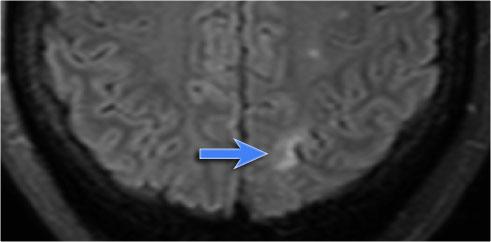

Xơ cứng thùy thái dương trong bên trái. Gliosis kín đáo của hải mã trái (mũi tên xanh dương) và teo não (mũi tên vàng).

Bệnh nhân 35 tuổi với động kinh thùy thái dương kháng trị.

MRI cho thấy tăng tín hiệu kín đáo của hải mã trái trên chuỗi xung FLAIR axial (mũi tên xanh dương) và teo hải mã trái trên hình ảnh coronal (mũi tên vàng).

Bệnh nhân được điều trị thành công bằng phẫu thuật cắt hạnh nhân – hải mã bên trái.